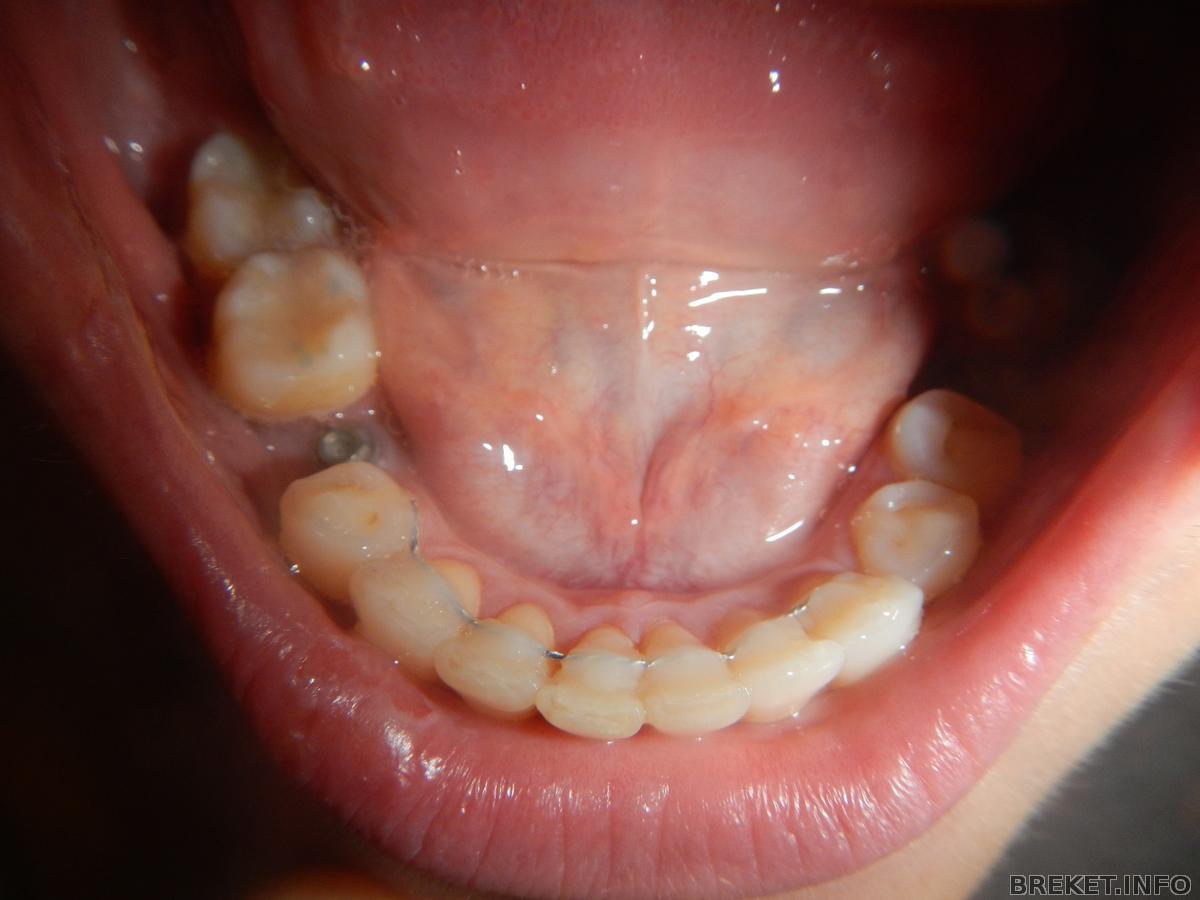

вчера НЧ сняли

вчера сняла низ БС

особого восторга не испытала..вот когда верх сниму конечно вздохну.

пока все болит(после полировки) неприятная процедураи вообще процесс жуткий и звук тоже брррр...и зубы какие то не мои. с внутренней стороны наклеен ретейнер-тоже не понравился процесс.(губу мне повредили) может настроение у нее было плохое